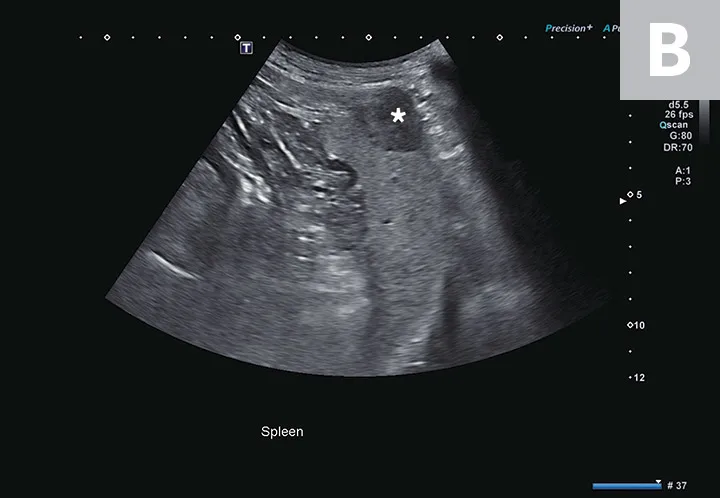

3. Abdominal Mass Identification in the Liver & Spleen

Hepatic and splenic nodules or masses can be primary or metastatic; can be benign or malignant; and may appear as a single mass, multiple masses, or diffusely infiltrative.10,11 Operator skill level, resolution of the ultrasound transducer, and echogenicity of the surrounding parenchyma can impact detection of soft-tissue nodules.12 Common malignant hepatic and splenic neoplasms include hepatocellular carcinoma, hemangiosarcoma, lymphoma, and histiocytic sarcoma. Common benign changes in the liver and spleen include hyperplasia, myelolipoma, hematoma, lymphoid hyperplasia, and extramedullary hematopoiesis.12,13 A large hepatic mass and peritoneal effusion are more often associated with neoplasia than a benign growth in the liver.13 In the spleen, nodules 1 to 2 cm in diameter, multiple targetoid lesions (hyperechoic center with hypoechoic rim), and peritoneal effusion are associated with neoplasia.14 Hepatic and splenic masses can have diverse characteristics, including well- or poorly circumscribed margins, variable echogenicity, fluid cavitation, and mineralization (Figure 3).

FIGURE 3

Transverse image of the right liver in a dog with a hyperechoic and multicavitary liver mass (A; asterisk) adjacent to a normal portion of liver (arrow). Deep (ie, bottom of the image) to the liver and the mass, the diaphragm appears as a hyperechoic line. Hypoechoic mass (B; asterisk) protruding from the splenic capsule.